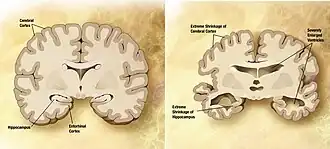

Comparação entre um cérebro idoso normal (esquerda) e o cérebro de uma pessoa com Alzheimer (direita), estando assinaladas as características diferenciadoras

A doença de Alzheimer é caracterizada pela perda de neurónios e sinapses no córtex cerebral e em determinadas áreas subcorticais. Esta perda provoca a atrofia das áreas afetadas, incluindo degeneração no lobo temporal, no lobo parietal e em partes do lobo frontal e do giro do cíngulo.[54] A degeneração ocorre também nos núcleos do tronco cerebral, como o cerúleo.[90] Os estudos com IRM e TEP documentam diminuições no tamanho de determinadas áreas do cérebro à medida que a doença evolui de défice cognitivo ligeiro para Alzheimer, em comparação com imagens semelhantes de idosos saudáveis.[91][92]

Tanto as placas amiloides como os novelos neurofibrilares são claramente observáveis ao microscópio no cérebro de pessoas com Alzheimer.[93] As placas são depósitos densos e praticamente insolúveis de peptídeos beta amiloides e material celular no exterior e em redor dos neurónios. Os novelos são agregados de proteína tau associada aos microtúbulos que se tornou hiperfosforilada e se acumulou no próprio interior das células. Embora alguns idosos possam desenvolver placas e novelos devido ao processo de envelhecimento, o cérebro de pessoas com Alzheimer apresenta um número muito superior em áreas específicas, como no lobo temporal.[94] Os corpos de Lewy não são incomuns em pessoas com Alzheimer.[95]